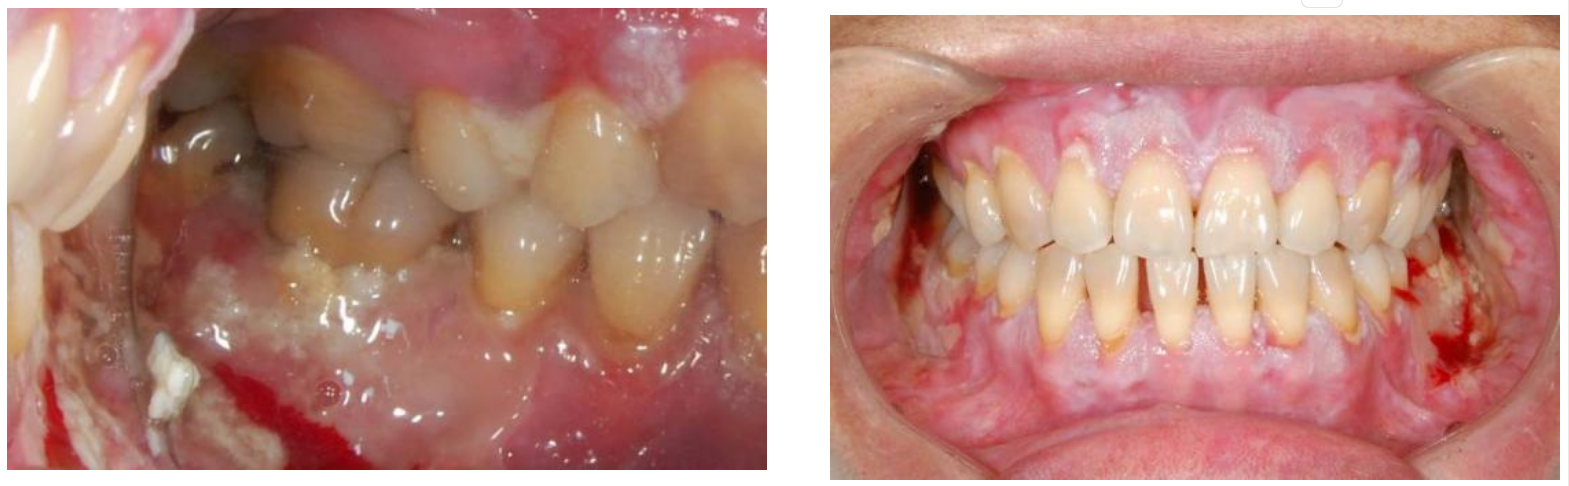

cGVHD不再单纯以移植后100天来划分,而是根据临床表现界定,最早可出现在移植后2个月2,其中45%~83%的cGVHD患者会出现口腔受累,而约20%的患者其cGVHD仅单独表现在口腔3。口腔cGVHD可累及口腔任何部位的黏膜,其特征性表现为口腔苔藓样损害——黏膜上出现网状或树枝状白色条纹4-5,外观类似植物苔藓而得名。在此基础上,病变可表现为黏膜红斑、糜烂、溃疡、假膜形成、萎缩,并伴随小唾液腺囊肿5。患者的主观症状多样,包括但不限于疼痛、口干、味觉改变以及对辛辣、酸性食物的敏感,晚期可出现张口受限6。这些表现并非孤立存在,而是共同构成了一张严重影响患者身心健康的网络。

溃疡形成及苔藓样损害(图片源自陶人川教授团队)

cGVHD口腔表现:红斑、苔藓样损害、溃疡及假膜形成(图片源自陶人川教授团队)